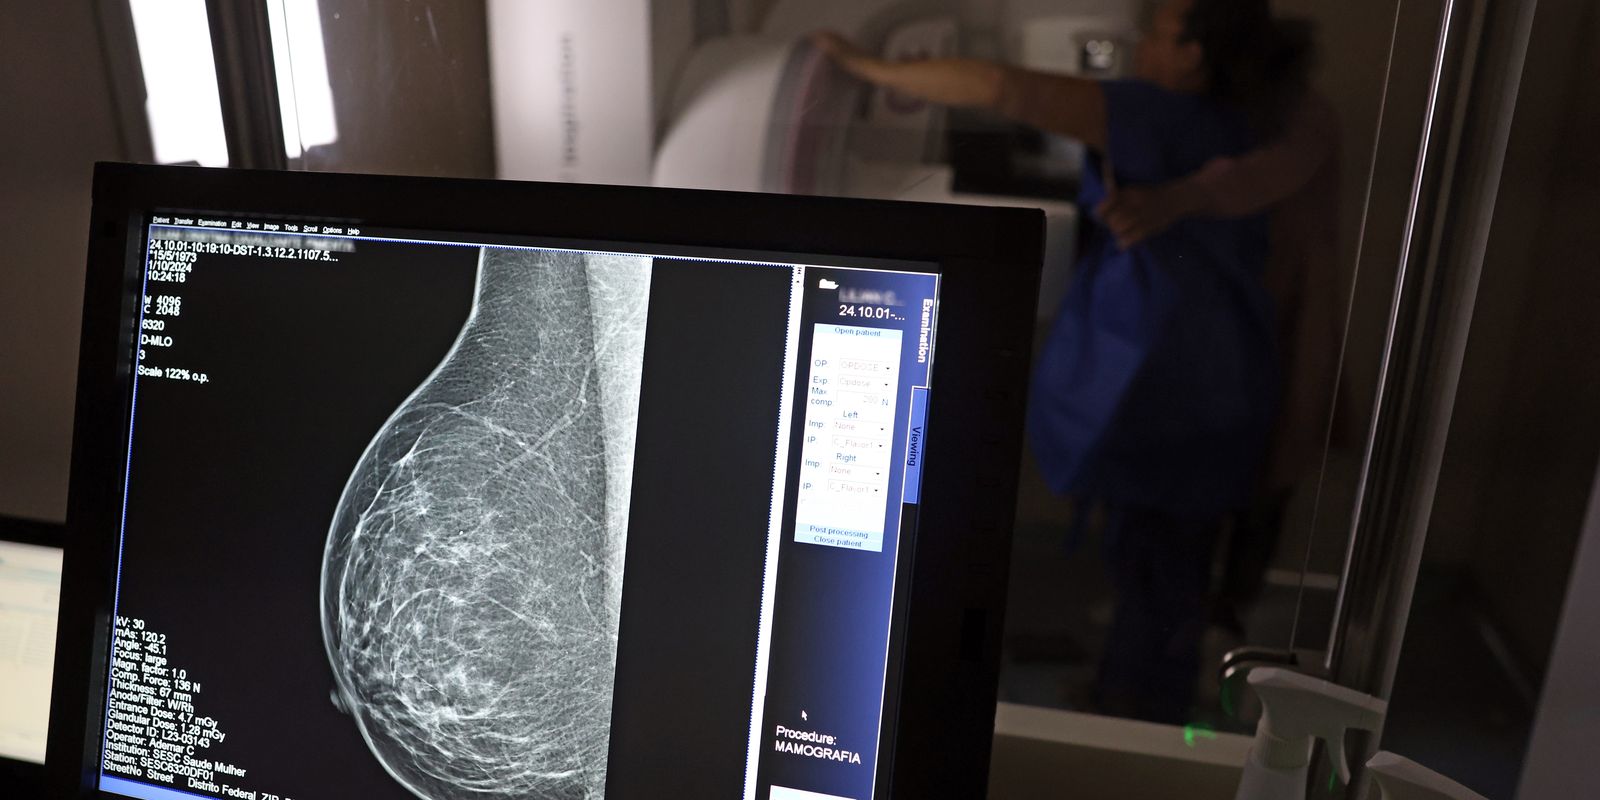

O Ministério da Saúde passou a recomendar o acesso a mamografia, via Sistema Único de Saúde (SUS), para mulheres de 40 a 49 anos – mesmo que não haja sinais ou sintomas de câncer de mama. De acordo com a pasta, a faixa etária concentra 23% dos casos da doença, e a detecção precoce aumenta as chances de cura.

Até então, a orientação era que o exame fosse feito a partir dos 50 anos.

A medida faz parte de um conjunto de ações anunciadas nesta terça-feira (23) voltado para a melhoria do diagnóstico e da assistência. A recomendação para mulheres a partir dos 40 anos é que o exame seja feito sob demanda, em decisão conjunta com o profissional de saúde.

As mamografias via SUS em pacientes com menos de 50 anos, de acordo com a pasta, representam 30% do total, o equivalente a mais de 1 milhão apenas no ano de 2024.

Outra medida anunciada é a ampliação da faixa etária para o rastreamento ativo – quando a mamografia é solicitada de forma preventiva a cada dois anos. A idade limite, até então, era 69 anos. Agora, passa a ser 74 anos. Dados do ministério revelam que quase 60% dos casos de câncer de mama estão concentrados entre 50 e 74 anos.

Os números mostram que, em 2024, cerca de 4 milhões de mamografias para rastreamento e 376,7 mil exames diagnósticos foram realizados no SUS.